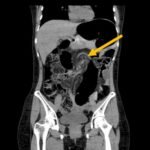

Computed tomography (CT) of the abdomen and pelvis was obtained revealing a colonic volvulus in the left mid to upper abdomen (blue arrow) involving the distal transverse colon and descending colon, with gaseous colonic distention to 8.5 cm (red arrow). The characteristic “whirl pattern” is also present (yellow arrow). These findings are suggestive of a high-grade colonic obstruction. It was without evidence of pneumoperitoneum, pneumatosis, or drainable collection. Of note, a 3.6 cm dermoid tumor is also observable in the left adnexa (green arrow).

Patients with sigmoid volvulus present with slow onset and progressive abdominal pain, nausea, abdominal distention, and constipation. Vomiting is also common but normally occurs several days after the initial onset of pain.5 Computed tomography is the preferred method of diagnosis with a sensitivity of 71%.6 Diagnostic findings include a “whirl pattern,” which is caused by the twisting of the sigmoid colon around its mesocolon, and a “bird-beak” appearance of the afferent and efferent colonic segments.7 Treatment of a sigmoid volvulus begins with a flexible sigmoidoscopy for decompression and detorsion, followed by definitive surgery to prevent recurrence.4 Without definitive surgery, recurrence rates of sigmoid volvulus has been reported as high as 90%.1 In this case, gastroenterology was consulted and patient was taken to the endoscopy suite for decompression and detorsion.